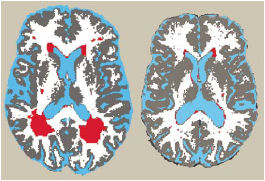

SPOTTED. Red zones highlight brain lesions—notable in scan at left and minimal in scan on right—imaged in magnetic resonance scans during a study of diet and the brain.